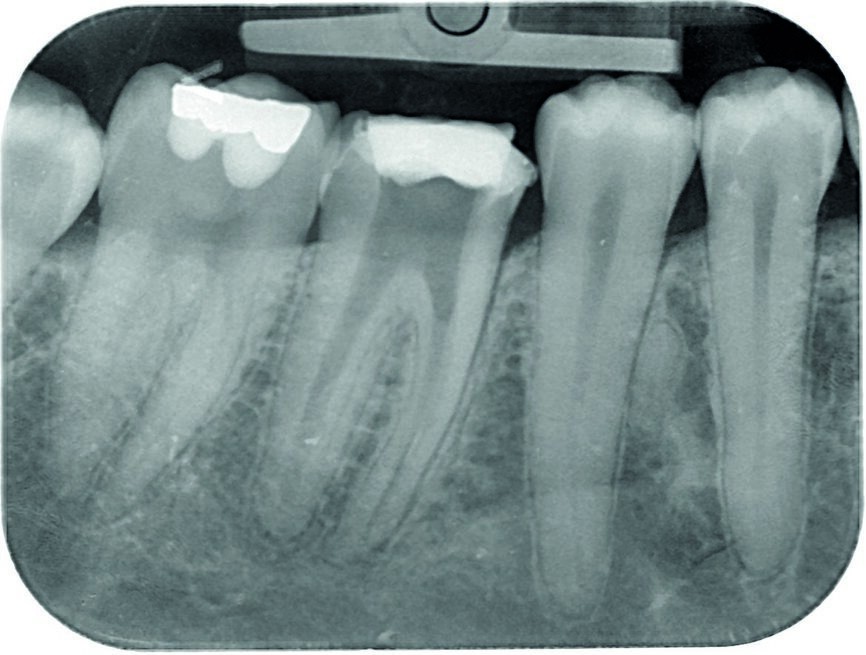

The calcium hydroxide paste was removed ten days later. The complete removal of paste from the root canal walls was accomplished by passive ultrasonic irrigation and 10% citric acid, using an endodontic tip (ESI, EMS) for more precise cleaning. Taking into consideration the extent of the apical root resorption, it was decided to perform orthograde MTA obturation of the distal canal space to arrest the resorption. The material was placed into the canals with the MAP System carrier (Produits Dentaires; Fig. 3) by the means of a 5 mm apical plug and was condensed vertically with a hand plugger. After radiographic examination of the accuracy of the apical plug (Fig. 4) and a setting period, the entire canal and the mesial canals were obturated with TotalFill BC (FKG Dentaire; Fig. 5). The orifices were adhesively sealed and the tooth was definitively restored with light-curing composite and prepared for a crown.

Fig. 5: Control radiograph after final obturation